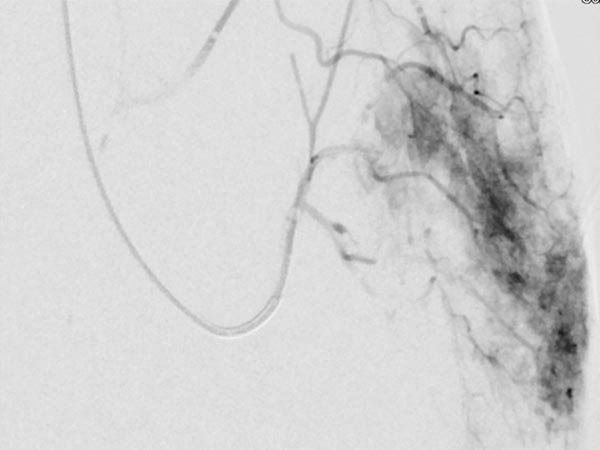

As there was still no tendency to regression of the tumor at the end of the 3rd year, embolization was performed after biopsy to induce involution. Digital subtraction angiography (DSA) shows a microcatheter superselectively introduced into a tumor vessel. The tumor is heavily perfused and lobulated, very early venous outflow, typical of an NICH.

Particle embolization with spherical particles 250 micrometers in size via the microcatheter inserted superselectively into the tumor.

More tumor vessels with blush-like diffuse enhancement, typical of a vascular tumor / NICH. All these vessels must be selectively embolized to induce involution.

Further selective particle embolization. The embolization particles mixed with contrast medium remain in the tumor vessels.

Overview angiography via the left external iliac artery also shows no remaining perfusion of the tumor anymore, thus the tumor vascularization is successfully and superselectively completely occluded. All non-pathological arteries are preserved.